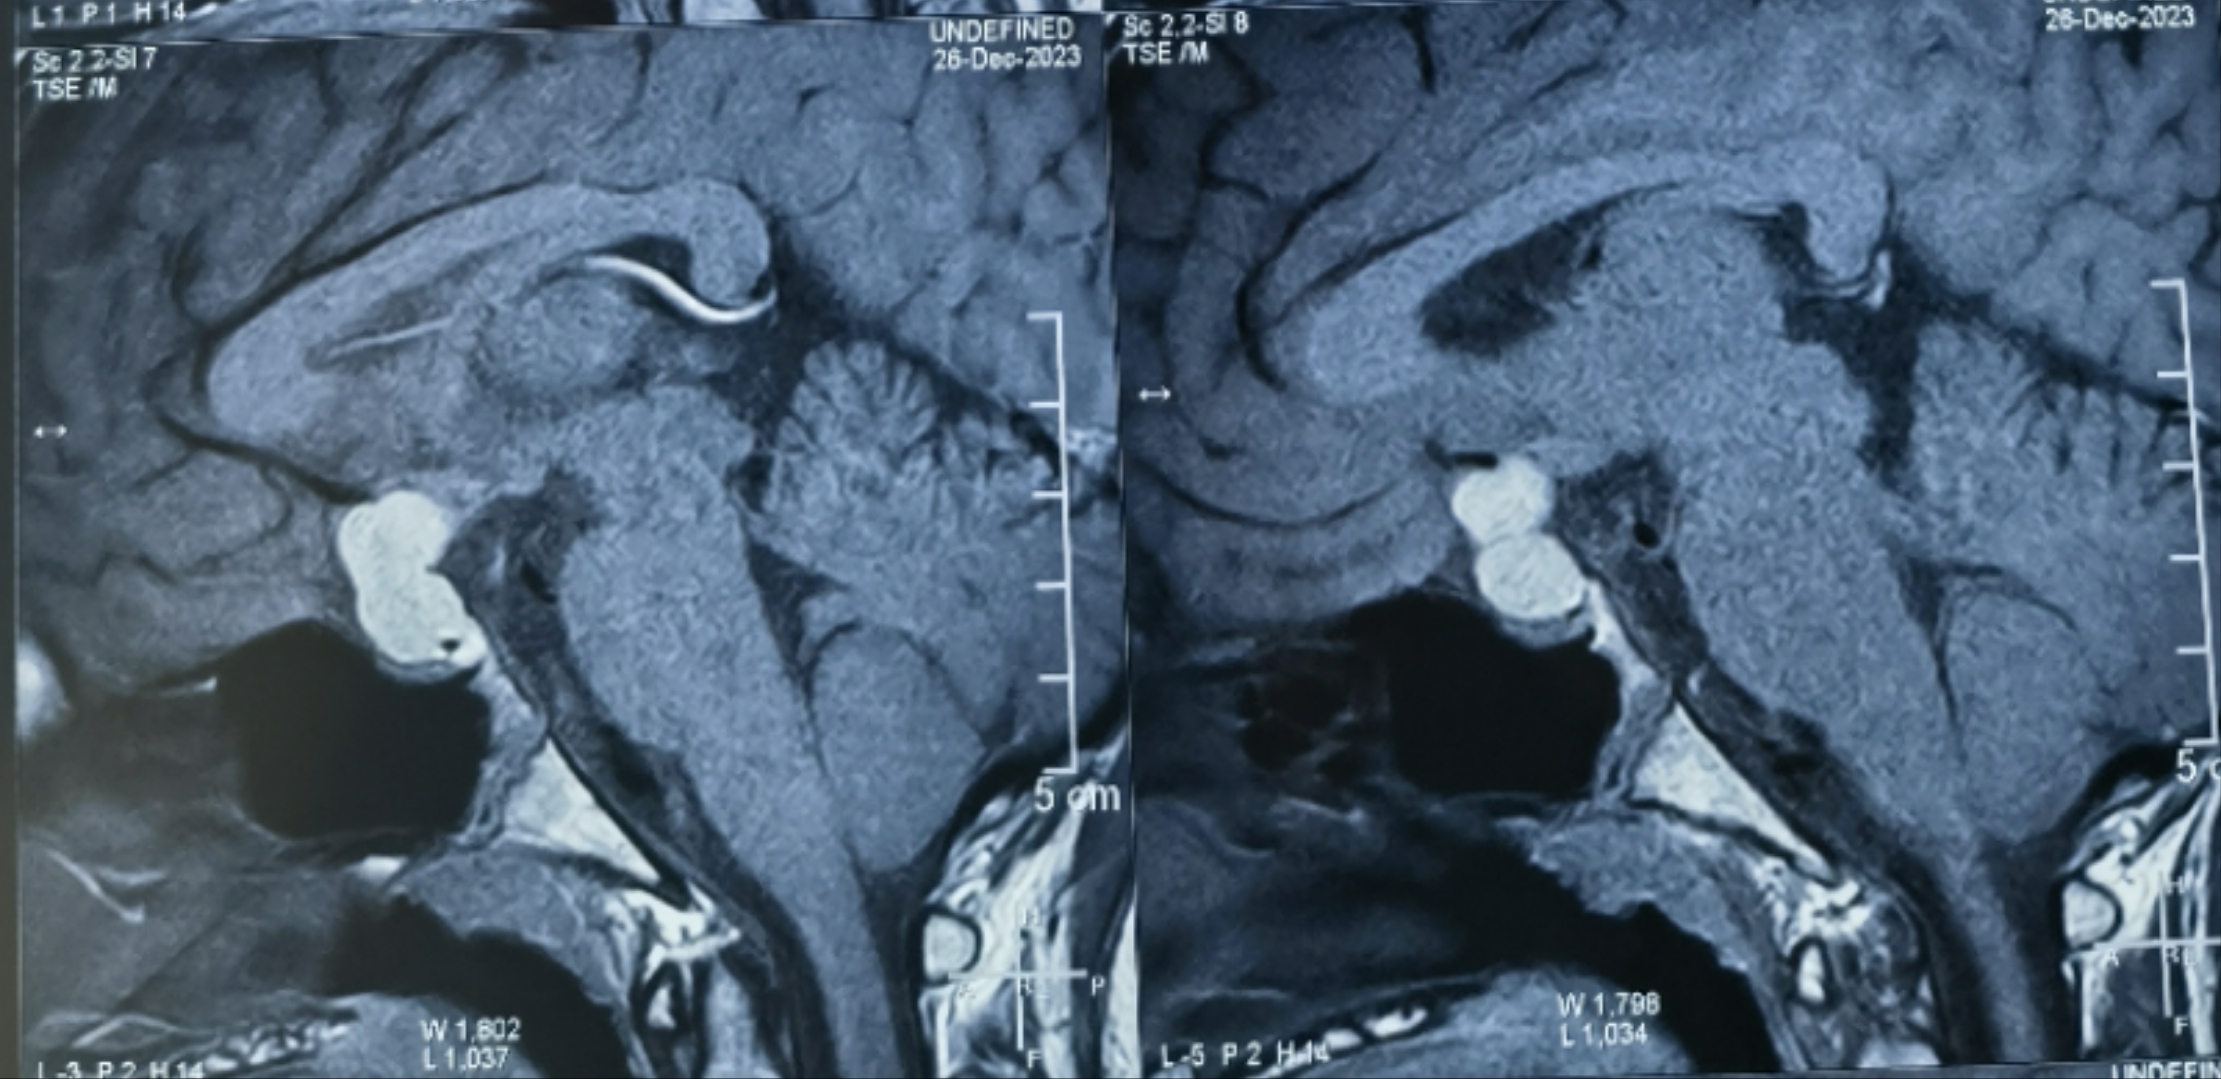

垂體瘤為什么會復發(fā)

垂體瘤為什么會復發(fā),今天跟大家聊一聊這個話題。最近遇到一位年輕的垂體瘤復發(fā)的患者,第一次發(fā)現是在2021年,術前有停經泌乳的表現,垂體激素化驗顯示泌乳素升高,做垂體增強磁共振發(fā)現腫物,診斷為泌乳素腺瘤??诜幬镏委煱肽晖=浢谌闆]有改善,隨后又出現視力模糊的癥狀,復查垂體增強磁共振發(fā)現腫物增大,壓迫視神經。這時候做了第一次經鼻內鏡垂體瘤的手術,術后效果很明顯,停經泌乳癥狀消失,視力也得到改善。一年以后2022年時復查垂體增強磁共振顯示垂體大小正常,抽血化驗垂體激素也未見異常。2023年7月開始出現陣發(fā)性頭痛,隨后再次出現視力模糊,但這次沒有出現停經泌乳改變。復查垂體增強磁共振提示有垂體瘤復發(fā)跡象,但是腫物大小還未對視神經造成明顯壓迫。垂體激素化驗正常。10月份再次復查顯示垂體瘤繼續(xù)生長,伴局部卒中出血,明顯壓迫視神經,隨后做了第二次經鼻內鏡手術,術后恢復良好(見下圖),順利出院。那么究竟是什么原因導致垂體瘤復發(fā)呢?目前還沒有明確的致病機制,但總的來說,應從以下幾個方面來分析:1.對于有功能的垂體瘤,通俗來講就是垂體分泌的激素中一種或幾種激素出現異常,這種異常會反饋性的造成垂體瘤細胞異常增生,從而導致垂體瘤復發(fā)。在這種情況下,無論第一次手術切除率是否滿意,都應監(jiān)測垂體激素的變化,這種垂體瘤復發(fā)時一般生長較快。2.對于無功能性垂體瘤,第一次手術全切后一般很少復發(fā),即使復發(fā)腫瘤生長也很慢。但如果第一次手術未實現全切,術后應注意影像學隨訪監(jiān)測腫瘤是否復發(fā)。在這例患者中,雖然第一次為有功能性垂體瘤,但是在第二次復發(fā)過程中未發(fā)現垂體激素異常,腫瘤體積變大的主要原因還是因為垂體瘤卒中所致。如果發(fā)現垂體瘤復發(fā),我們應該采取什么樣的診療策略呢?1.對于小的,無功能性的垂體瘤,以觀察為主,可以定期復查垂體激素以及垂體增強磁共振。這種垂體瘤一般生長緩慢,可以長期隨訪。2.對于小的,有功能性的垂體瘤,比如泌乳素腺瘤或者生長激素腺瘤,可以應用相對應的藥物,溴隱亭或生長抑素等來控制腫瘤的生長。3.對于腫瘤較大,已經壓迫周圍神經的,可采取二次手術。絕大多數復發(fā)垂體瘤手術方案首選經鼻內鏡手術,部分病例需采取開顱手術或者聯合手術。復發(fā)垂體瘤治療有哪些注意事項?由于是二次手術,解剖結構不清晰會造成手術困難,造成出血和神經副損傷風險的增加。其次,由于鞍底結構已經破壞,二次手術以后腦脊液漏的風險也會增加。最后,二次手術的全切率較第一次也會降低。建議垂體瘤患者朋友們不要忽視定期復查的重要作用,及早發(fā)現腫瘤復發(fā),為下一步治療爭取寶貴的時間。也祝大家早日康復!